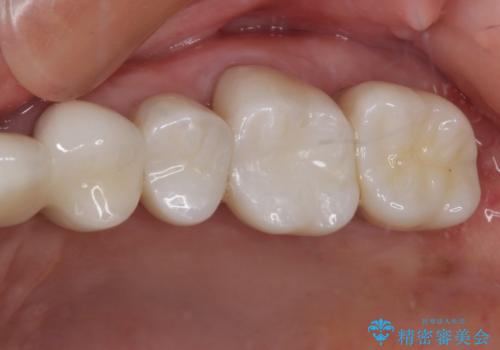

ゴールドインレーは銀歯のインレーやセラミックインレーと比べ、「技工操作の精度が高く、適合が著しく良い」というメリットがあります。特に上の奥歯は歯科医師の操作が行いにくいため、「適合の良さ」は再治療のリスクを防ぐ上でとても重要な要素となります。

上の奥歯は金属色が見えることもないため、審美的な問題は全くありません。

咬み心地はとても良好で、全く違和感がなく、患者様には大変満足していただきました。